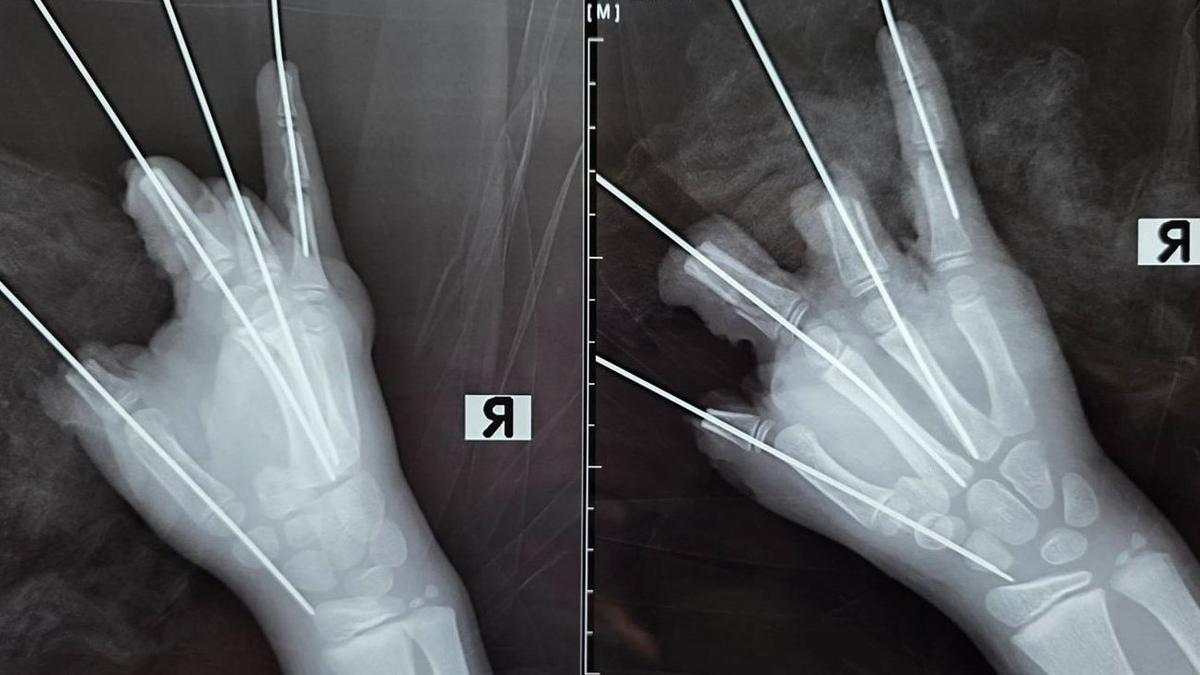

Детский микрохирург Антон Волков пояснил: специалисты сохранили максимально возможный объем тканей, однако повреждения оказались настолько серьезными, что полноценная реконструкция конечности невозможна. Врачи удалили свободно лежащие костные фрагменты, соединили отломки фаланг среднего и безымянного пальцев методом металлоостеосинтеза, провели щадящую обработку и сформировали культи на уровне проксимальных фаланг.